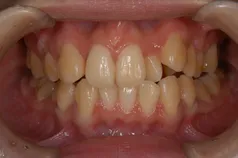

[症例]

矯正治療を行っています。

治療前は上下の歯が反対になっている所もあり、上の歯の真ん中から2本目の歯は矮小歯と言って、平均より小さな歯のため上唇が引っ込んで見えます。

インビザラインでマウスピース矯正後、オフィスホワイトニングを行い、矮小歯はラミネートベニアで修復しました。

綺麗な歯並びになるとともに、上顎の歯列のアーチが広がって、上唇がやや前方に出ることで自然な口元になりました。

- 治療期間: 1年6ヶ月

- 治療回数: 10回

- 費用: 120万円

- デメリット:治療後に矯正の後戻り防止のためのマウスピースを使用しなければならない